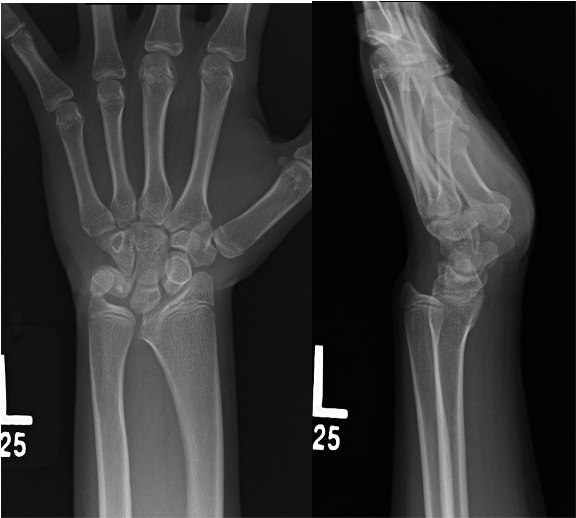

Deformity associated with madelung’s

<!--StartFragment-->

Volar carpal subluxation

proximal radial synostosis

increased radial inclination

volar tilt

volar-ulnar tethering of vickers ligament

<!--EndFragment-->

What is the treatment for this deformity

watch if they are young, deformity is small; assess with serial XR

Consider OR for pain or functional deformity

Physiolysis or Vickers release - open physis with progression

Radial ostotomy, vickers release, +/- ulnar ostoetomy, +/- ulnar epiphyseodesis